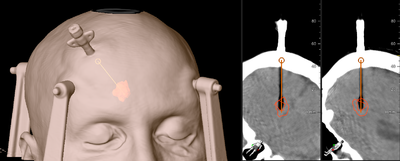

Her illustreret med et tilfælde af LITTAH, Ablation af amygdala og hippocampus som behandling mod tindingelaps-epilepsi.

På fohånd er der planlagt en stikkanal gennem hjernen gennem occipitallappen under ventrikelsystemet så hippocampus nås ved corpus og banen går i nederste del af hippocampus og frem til den nederste del af amygdala.

Koordinaterne fra computerprogrammet indstilles på den stereotaktiske rammes sterile overdel som passer ned på hovedringen.

En ekstra CT-scanning viser kateterets beliggenhed.